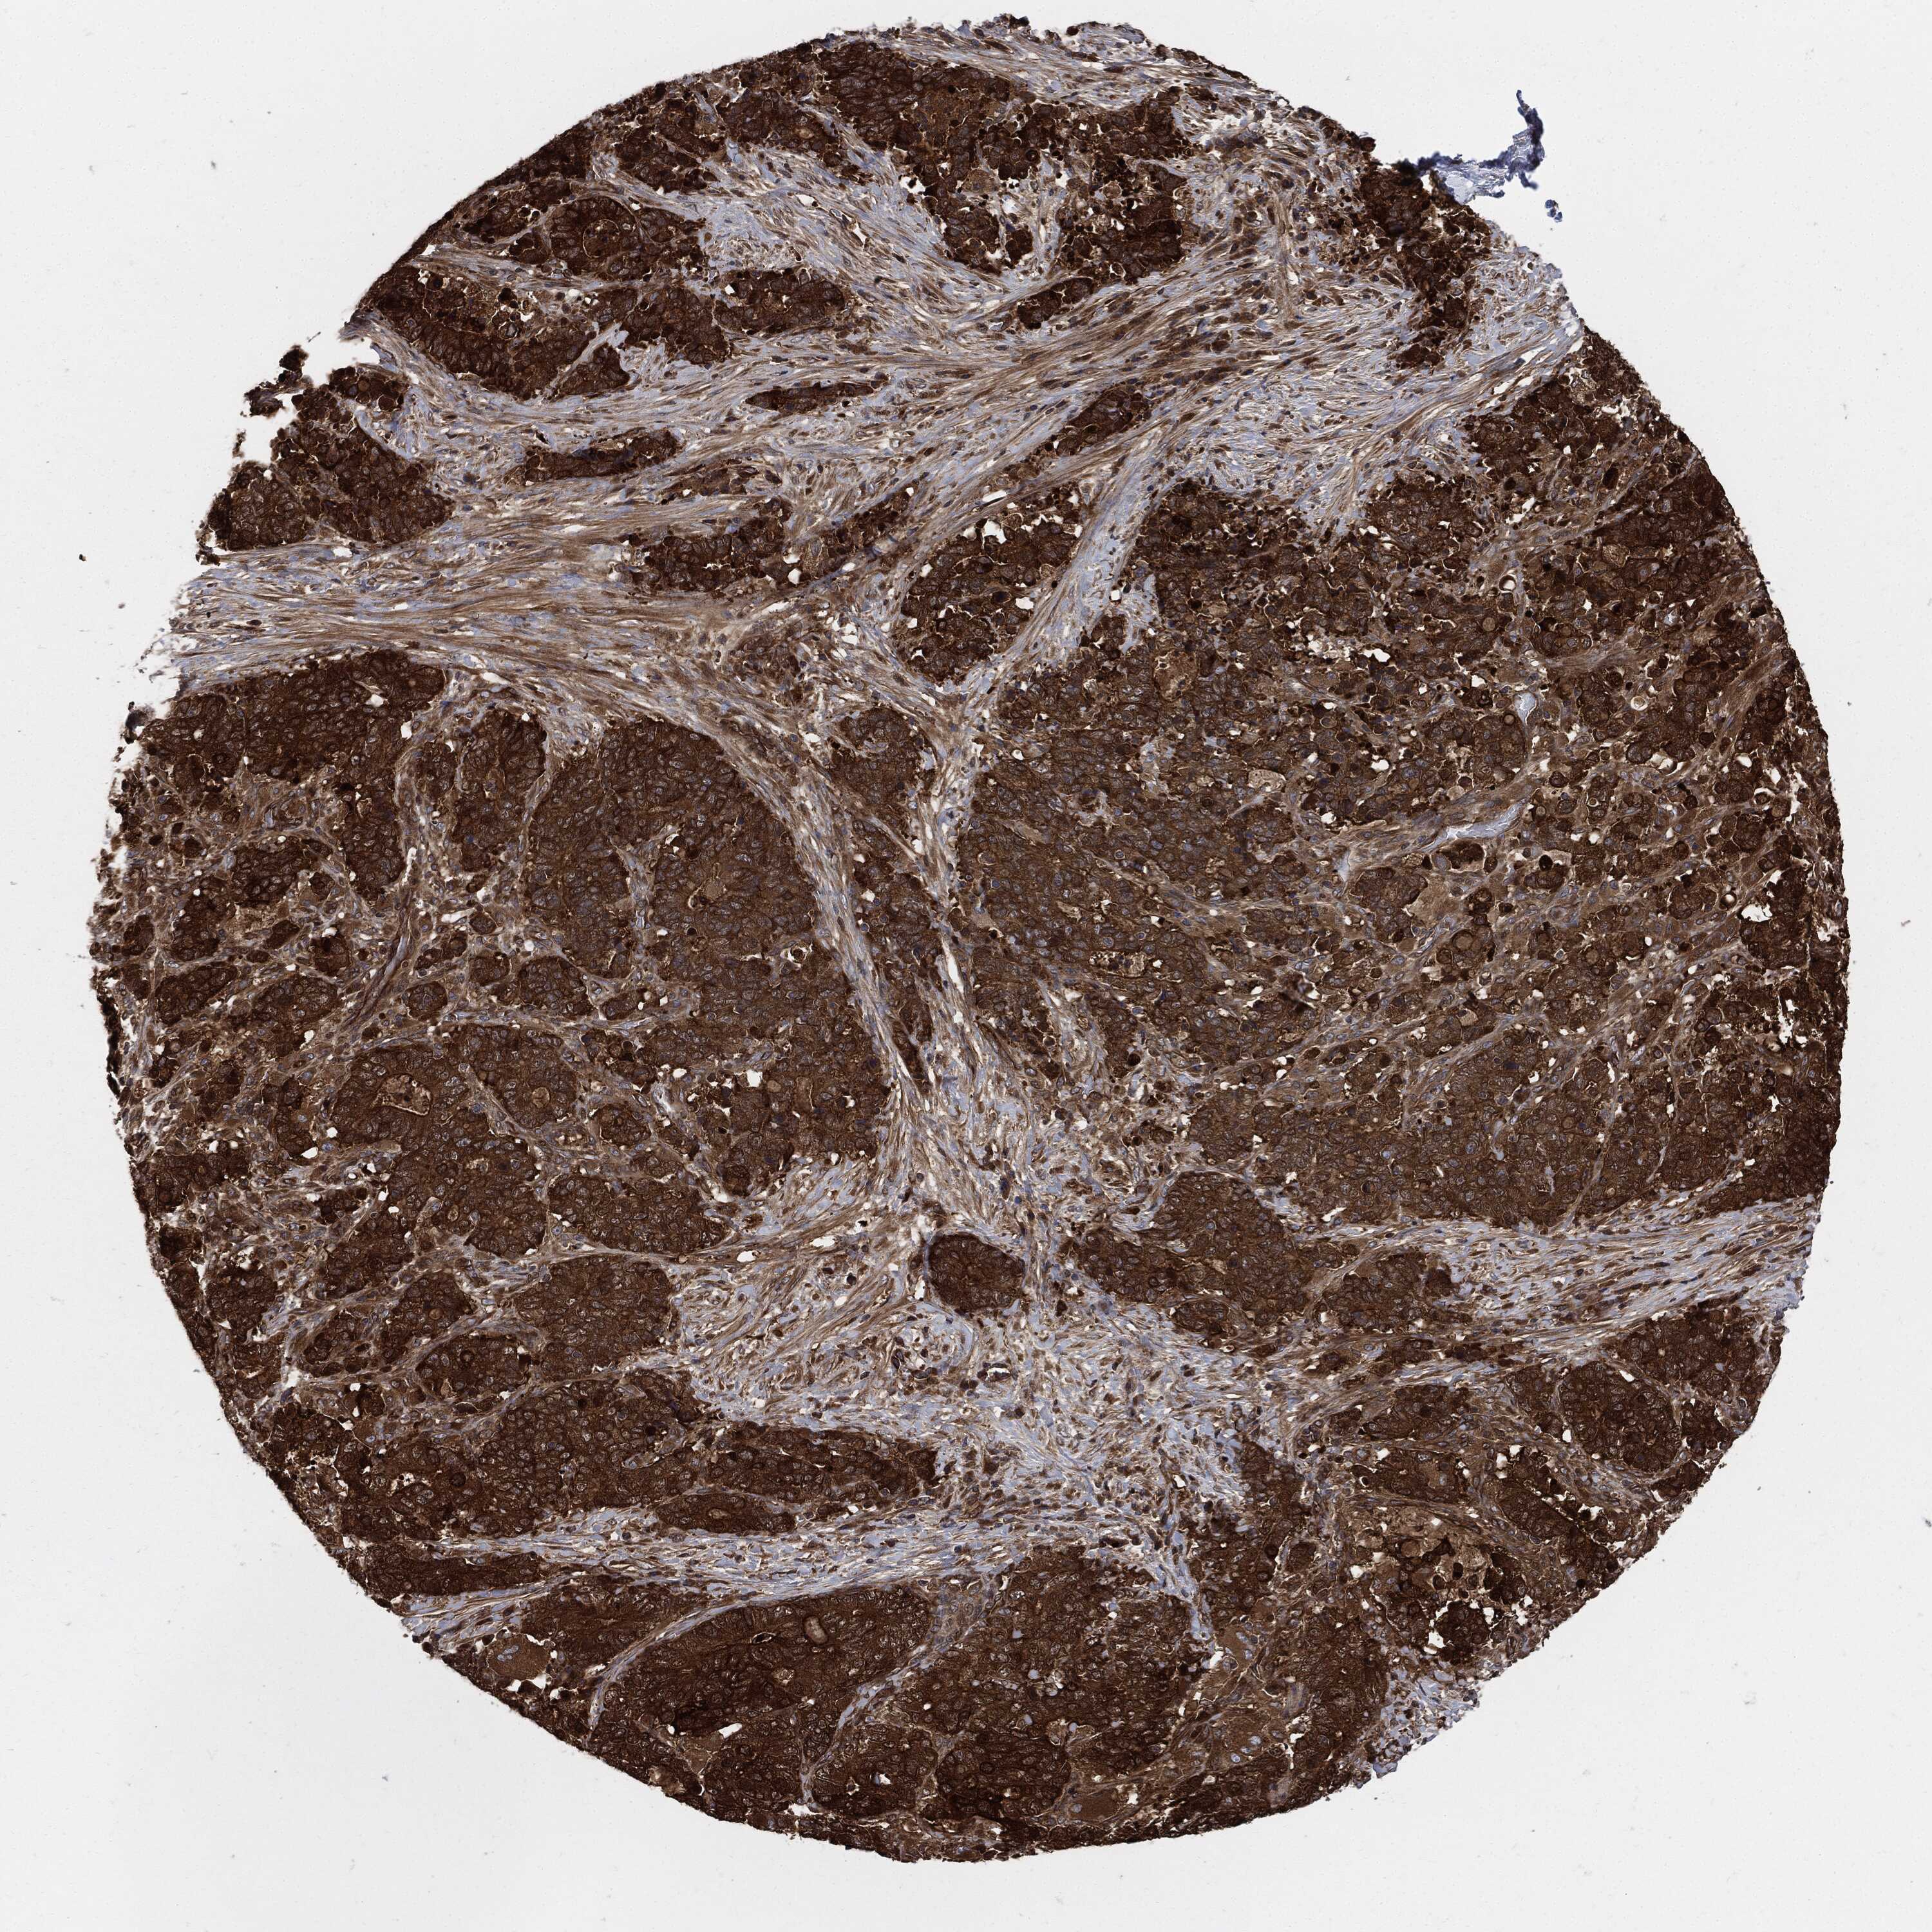

STOMACH CANCER - Protein expressioni

A mouse-over function shows sample information and annotation data. Click on an image to view it in a full screen mode. Samples can be filtered based on level of antibody staining by selecting one or several of the following categories: high, medium, low and not detected. The assay and annotation is described here.

Note that samples used for immunohistochemistry by the Human Protein Atlas do not correspond to samples in the TCGA dataset.

Antibody stainingi

Antibody staining in the annotated cell types in the current human tissue is reported as not detected, low, medium, or high, based on conventional immunohistochemistry profiling in selected tissues. This score is based on the combination of the staining intensity and fraction of stained cells.

Each image is clickable and will lead to virtual microscopy that enables deeper exploration of all samples and also displays staining intensity scores, fraction scores and subcellular localization as well as patient and tissue information for each sample.

HPA030419

HPA030420

HPA030422

CAB025196

CAB080286

CAB080287

Staining

High

Medium

Low

Not detected

Intensity

Strong

Moderate

Weak

Negative

Quantity

>75%

75%-25%

<25%

None

Location

Nuclear

Cytoplasmic/membranous

Cytoplasmic/membranous,nuclear

Adenocarcinoma, NOS

Adenocarcinoma, High grade